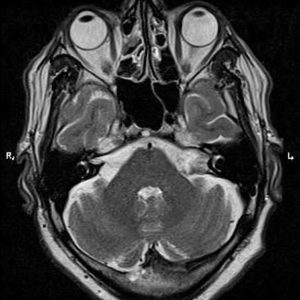

U dây VIII

Lượt xem: 140» 24-11-2018 -

U dây VIII

Lượt xem: 131» 24-11-2018 -

U dây VIII

Lượt xem: 143» 24-11-2018 -

U dây VIII

Lượt xem: 155» 24-11-2018 -

U dây VIII

Lượt xem: 124» 19-11-2018 -

U dây VIII

Lượt xem: 159» 05-11-2018 -

U dây VIII

Lượt xem: 239» 30-10-2018 -